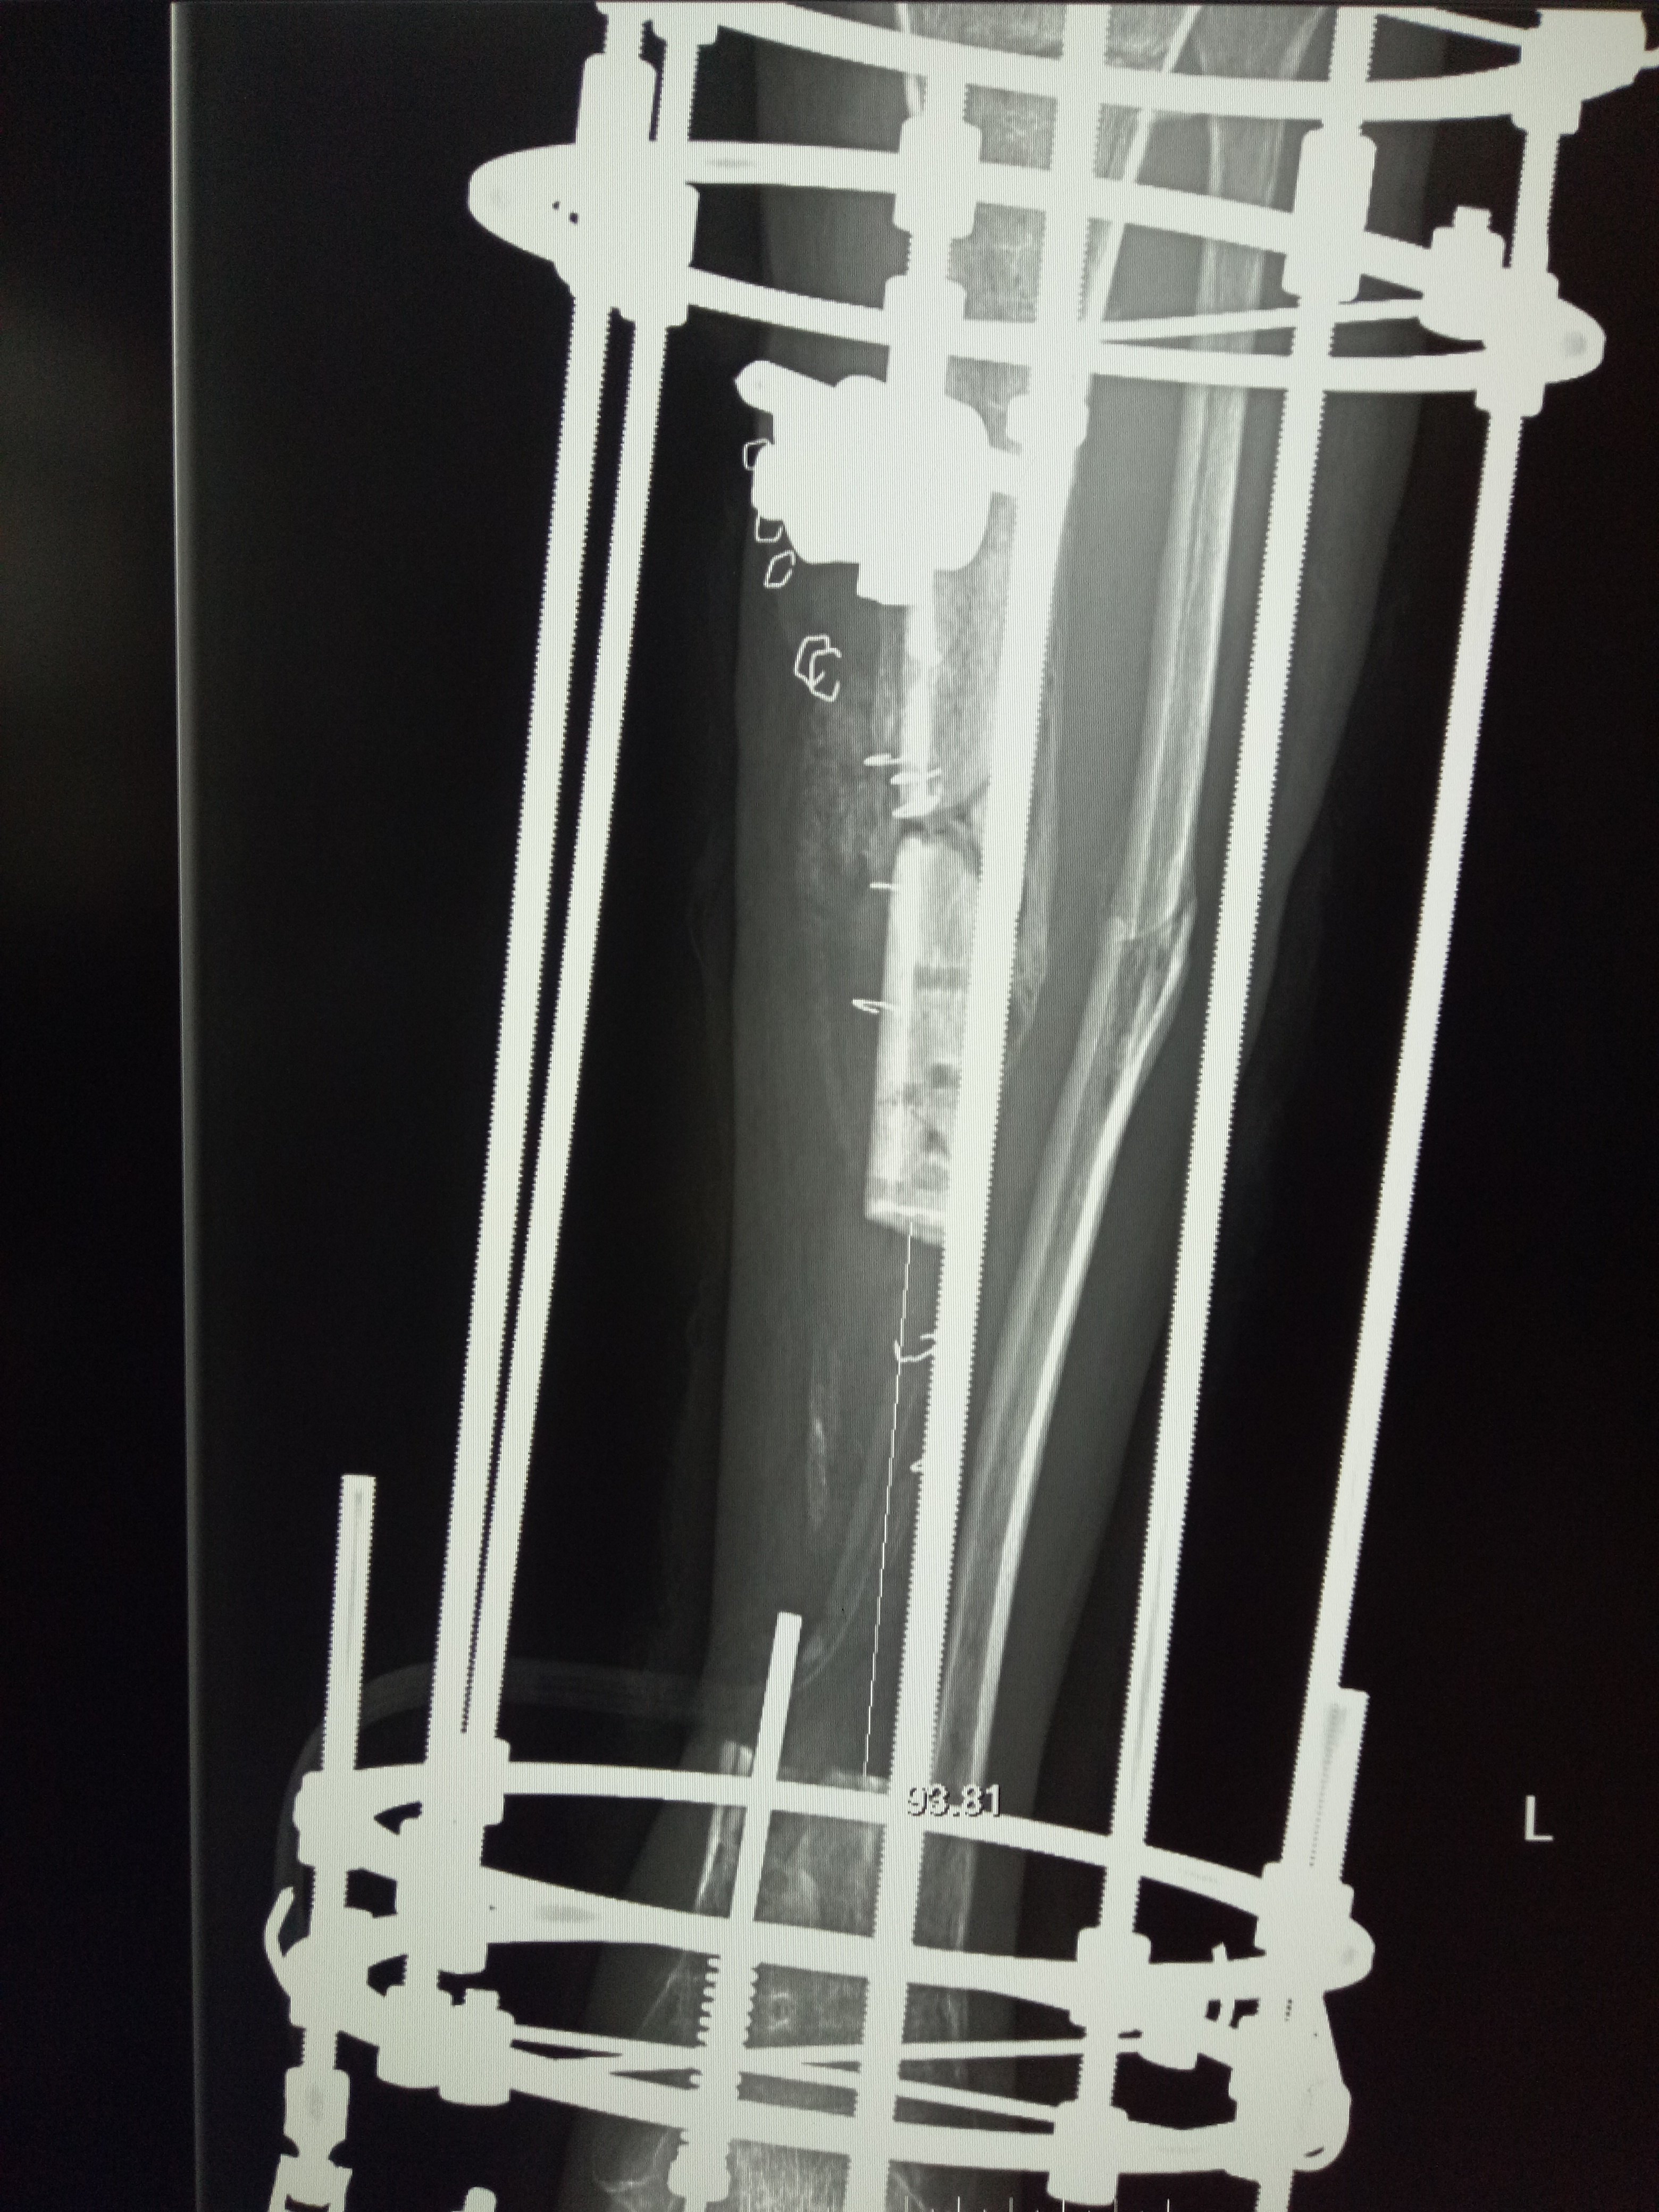

内外结合骨延长术治疗胫骨骨不连--典型病例报

547x600 - 50KB - JPEG

大段病骨切除同时截骨延长治疗胫骨感染性骨不

518x392 - 52KB - JPEG